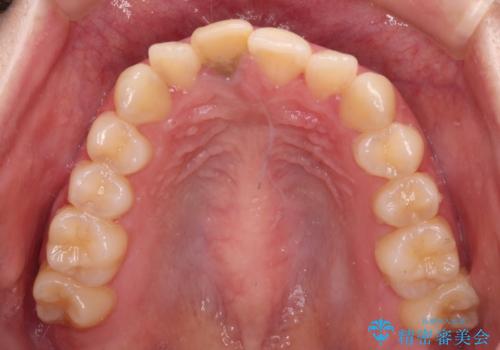

- 虫歯により神経を取り除いた前歯の変色が気になるとのことで来院された患者様です。

レントゲン写真より、歯根の炎症が認められなかったため、ファイバーコアによる土台築製後、オーダーメイドタイプのオールセラミッククラウンにて補綴することとしました。

あっという間に気になっていた変色が解決し、早く治療を始めれば良かったとおっしゃっていました。

オーダーメイドタイプのクラウンを選択いただいたので、まるで天然の歯と見間違うほど自然に仕上がり、患者様には大変満足していただきました。